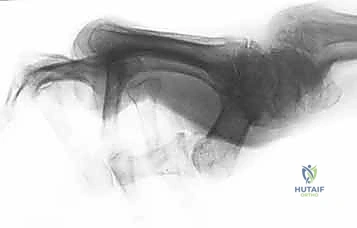

- التصوير الشعاعي (X-Rays):

- ضروري جداً لاستبعاد وجود كسور قلاعية (Avulsion Fractures) حيث ينفصل الوتر آخذاً معه قطعة من العظم، وكذلك لتقييم درجة تلف الغضاريف بسبب الروماتويد.

- الرنين المغناطيسي (MRI) أو الموجات فوق الصوتية (Ultrasound):

- تُستخدم في الحالات المعقدة لتقييم الأنسجة الرخوة والأوتار بدقة متناهية.